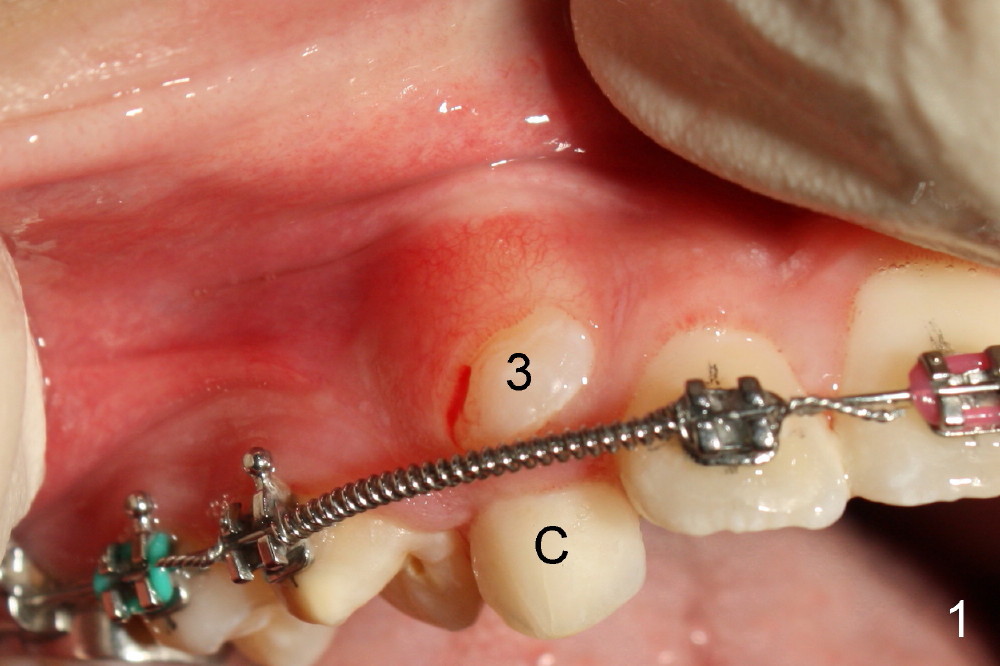

Three months post bracketing, spaces have been gained for U3s, which have erupted initially (Fig.1,2; arrowheads in Fig.2 denote the attached gingiva). UL C has exfoliated. The patient is 13 years old.

Two oblique incisions were made mesial and distal to UR3 (Fig.3). The mucoperiosteal flap (Fig.3 arrow; Fig.4 F) was raised and pushed apically for bracket placement. Following extraction of UR C, one-fourth inch elastics were placed between U3 and L3,4 (Fig.5,6). The patient was instructed to wear the elastics 24 hours per day. The upper wire is .018 ss with open coil springs, while lower .020.